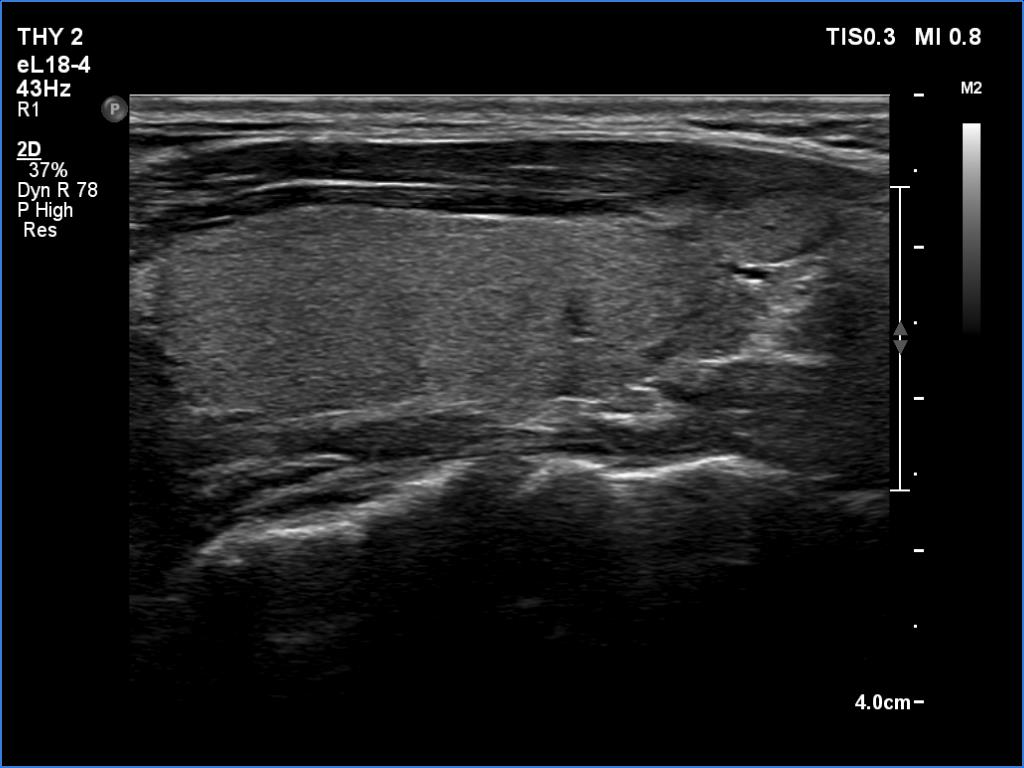

Ultrasound. Both lobes were echonormal and intact. The vascularity was average.

Diagnosis. A healthy thyroid with great probability.